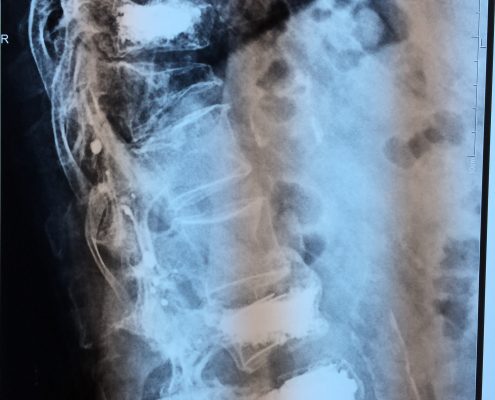

El sistema SpineJack® ha sido diseñado para la reducción anatómica de Fracturas Vertebrales por Compresión (FVC de tipo A1, A2 y A3 según la clasificación de Magerl), con o sin patologías subyacentes que afecten a la calidad del hueso, como la osteoporosis y las lesiones de origen oncológico (metástasis osteolítica o mieloma).

Diversos estudios clínicos y epidemiológicos han demostrado que existe correlación entre la deformación vertebral y problemas clínicos como la cifosis postraumática, que ha sido descrita como una de las deformidades postraumáticas potencialmente más graves. En este contexto, Vexim ha diseñado el implante SpineJack® para ofrecer al médico una solución totalmente controlada y completa para el tratamiento de las FVC, que permite primero una reducción anatómica y después una estabilización segura.